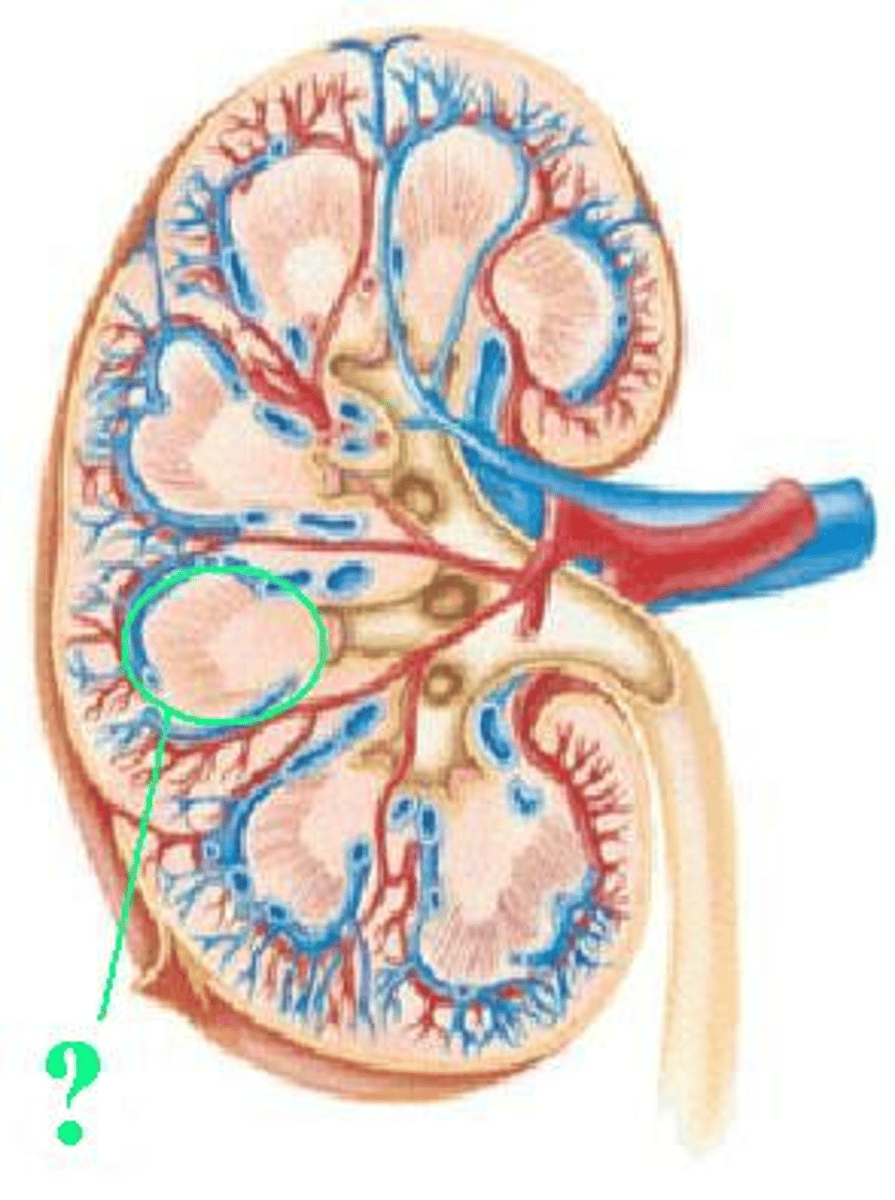

minor calyx

Identify the indicated structure.